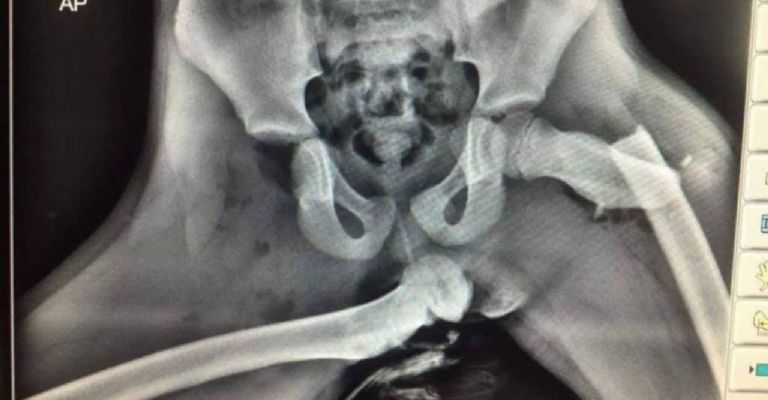

Uno de los errores más comunes y más peligrosos que se pueden cometer al ser copiloto es el hecho de querer subir las piernas a la zona del tablero del automóvil porque se podría pensar que es cómodo, pero puede ser una señal clara de peligro si existe algún tipo de accidente que pueda tomar en una mala posición a la persona, cómo sería en este caso.

La mayoría de los autos en la actualidad cuentan con algo que se conoce como "bolsa de aire frontal" o el llamado "air bag frontal", la cual se despliega y sale cuando se presenta un choque. Este es uno de los aspectos más importante de todos al estar mal posicionado.

Ahora, con esas bolsas de aire, si el copiloto no está en la posición correcta, pueden sufrir lesiones de gravedad por el simple hecho de no estar sentados correctamente en el automóvil.

La lesión de huesos por esta situación puede ser terrible. Crédito: CAPTURA DE PANTALLA